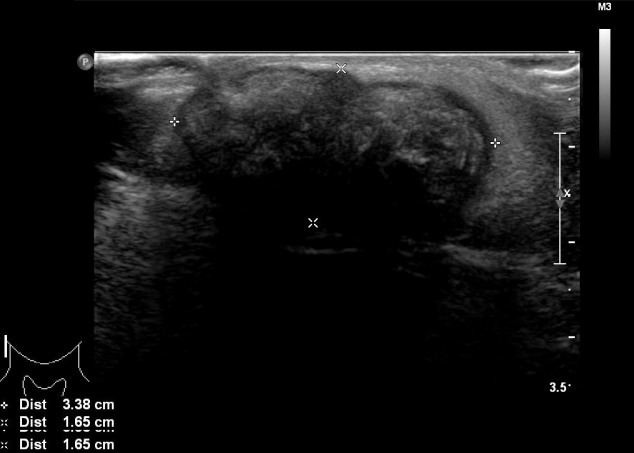

進(jìn)行超聲檢查以確定腫塊是否為腮腺腫瘤,并顯示與腮腺分離的異質(zhì)腫塊(圖 2)。 進(jìn)行了頸部對比增強(qiáng)計算機(jī)斷層掃描和超聲引導(dǎo)穿刺活檢。 在右下頜角,它表現(xiàn)為邊界清楚、分葉狀和不均勻強(qiáng)化的腫瘤,在皮下脂肪層和淺表肌肉腱膜系統(tǒng)中有鈣化部分(圖 3)。 穿孔活檢顯示與毛母質(zhì)瘤一致的特征,并且在超聲引導(dǎo)下對頸部淋巴結(jié)進(jìn)行抽吸活檢時未發(fā)現(xiàn)腫瘤細(xì)胞。

圖 2:超聲檢查顯示與腮腺分離的異質(zhì)性病變